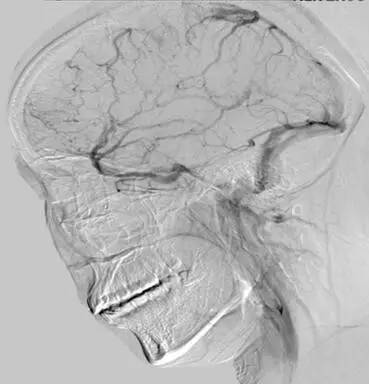

诊治经过:考虑存脑疝,予开颅血肿清除+去骨瓣减压术,,术后予降颅压对症治疗。考虑患者可能存颅内静脉窦血栓,行MRV及全颈脑血管造影术,示“左侧横窦闭塞 矢状窦、右侧横窦血栓形成”。予华法林抗凝治疗。出院PT-INR:2.11。门诊随访中。

▼影像资料

▼全颈脑血管造影术。